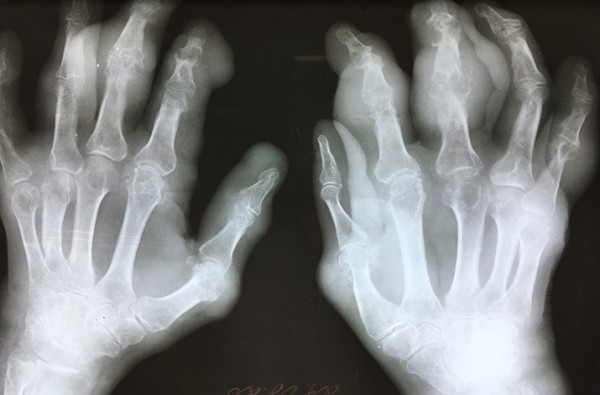

Фото носит иллюстративный характер. Из открытых источников.

Характерная клиника начальной подагры не вызывает сомнений в диагнозе. Трудности в диагностике возникают при первичном обращении пациентов с многолетней подагрой, а также при атипичном поражении суставов. Многолетняя подагра характеризуется множественным поражением суставов, упорным, длительным течением, маскируется под другие болезни суставов. За свою долгую практику довелось наблюдать подагрическое поражение сухожилий и пяток, фасеточных суставов позвоночника, грудино-ключичных сочленений, плечевых суставов.

В сложных диагностических случаях помогает нахождение подагрических тофусов, которые могут быть размером от нескольких миллиметров до невероятно огромных. Подагрические тофусы — это по сути склады мочевой кислоты, куда она собирается при избытке в крови. Чаще всего тофусы появляются над суставами, в частности, в области локтевых суставов, нередко на ушных раковинах.

Работая со множеством пациентов, я наблюдал самые разные случаи образования тофусов, как редкие, так и типичные. Многие из них фотографировал и могу поделиться частью снимков (см. фото).